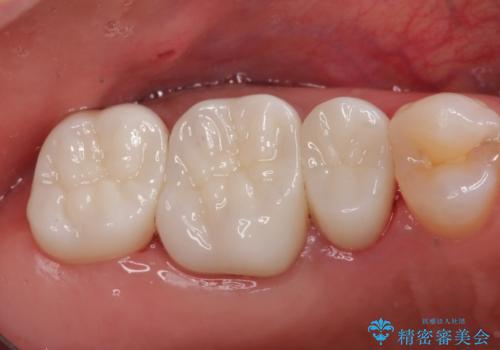

笑った時に見える金属を白くしたい

目立つ銀歯を白くしたい 奥歯のセラミック治療